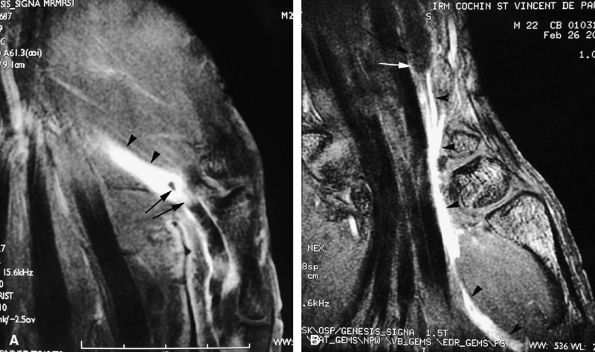

FIGURE 11.43 ● Acute open injury of the flexor pollicis longus tendon. (A) On these coronal post-contrast fat-suppressed T1-weighted images, the distal end of the tendon can be seen at the entry of the digital canal (arrows). (B) The proximal end is seen at the level of the radiocarpal joint (arrows). The tendon gap measures 6 cm. The empty tendon sheath shows significant synovitis (arrowheads in both images).

FIGURE 11.44 ● Acute rupture of the flexor digitorum profundus (FDP) tendon of the little finger in zone II. Coronal (A) and axial (B) post-contrast fat-suppressed T1-weighted images show retraction of a flexible proximal end (arrows) wrapping around the FDS tendon (asterisk).

FIGURE 11.47 ● Jersey finger. (A) Sagittal T2-weighted image. (B) Coronal post-contrast T1-weighted images. (C) Axial T1-weighted image. Distal avulsion of the FDP tendon is shown with the proximal end (white arrows) at the metacarpophalangeal joint (type I). The tendon is wavy in the palm (arrowheads). The empty digital canal (in C) may mimic a remnant tendon, but the FDS tendon (asterisk) is alone in the canal.